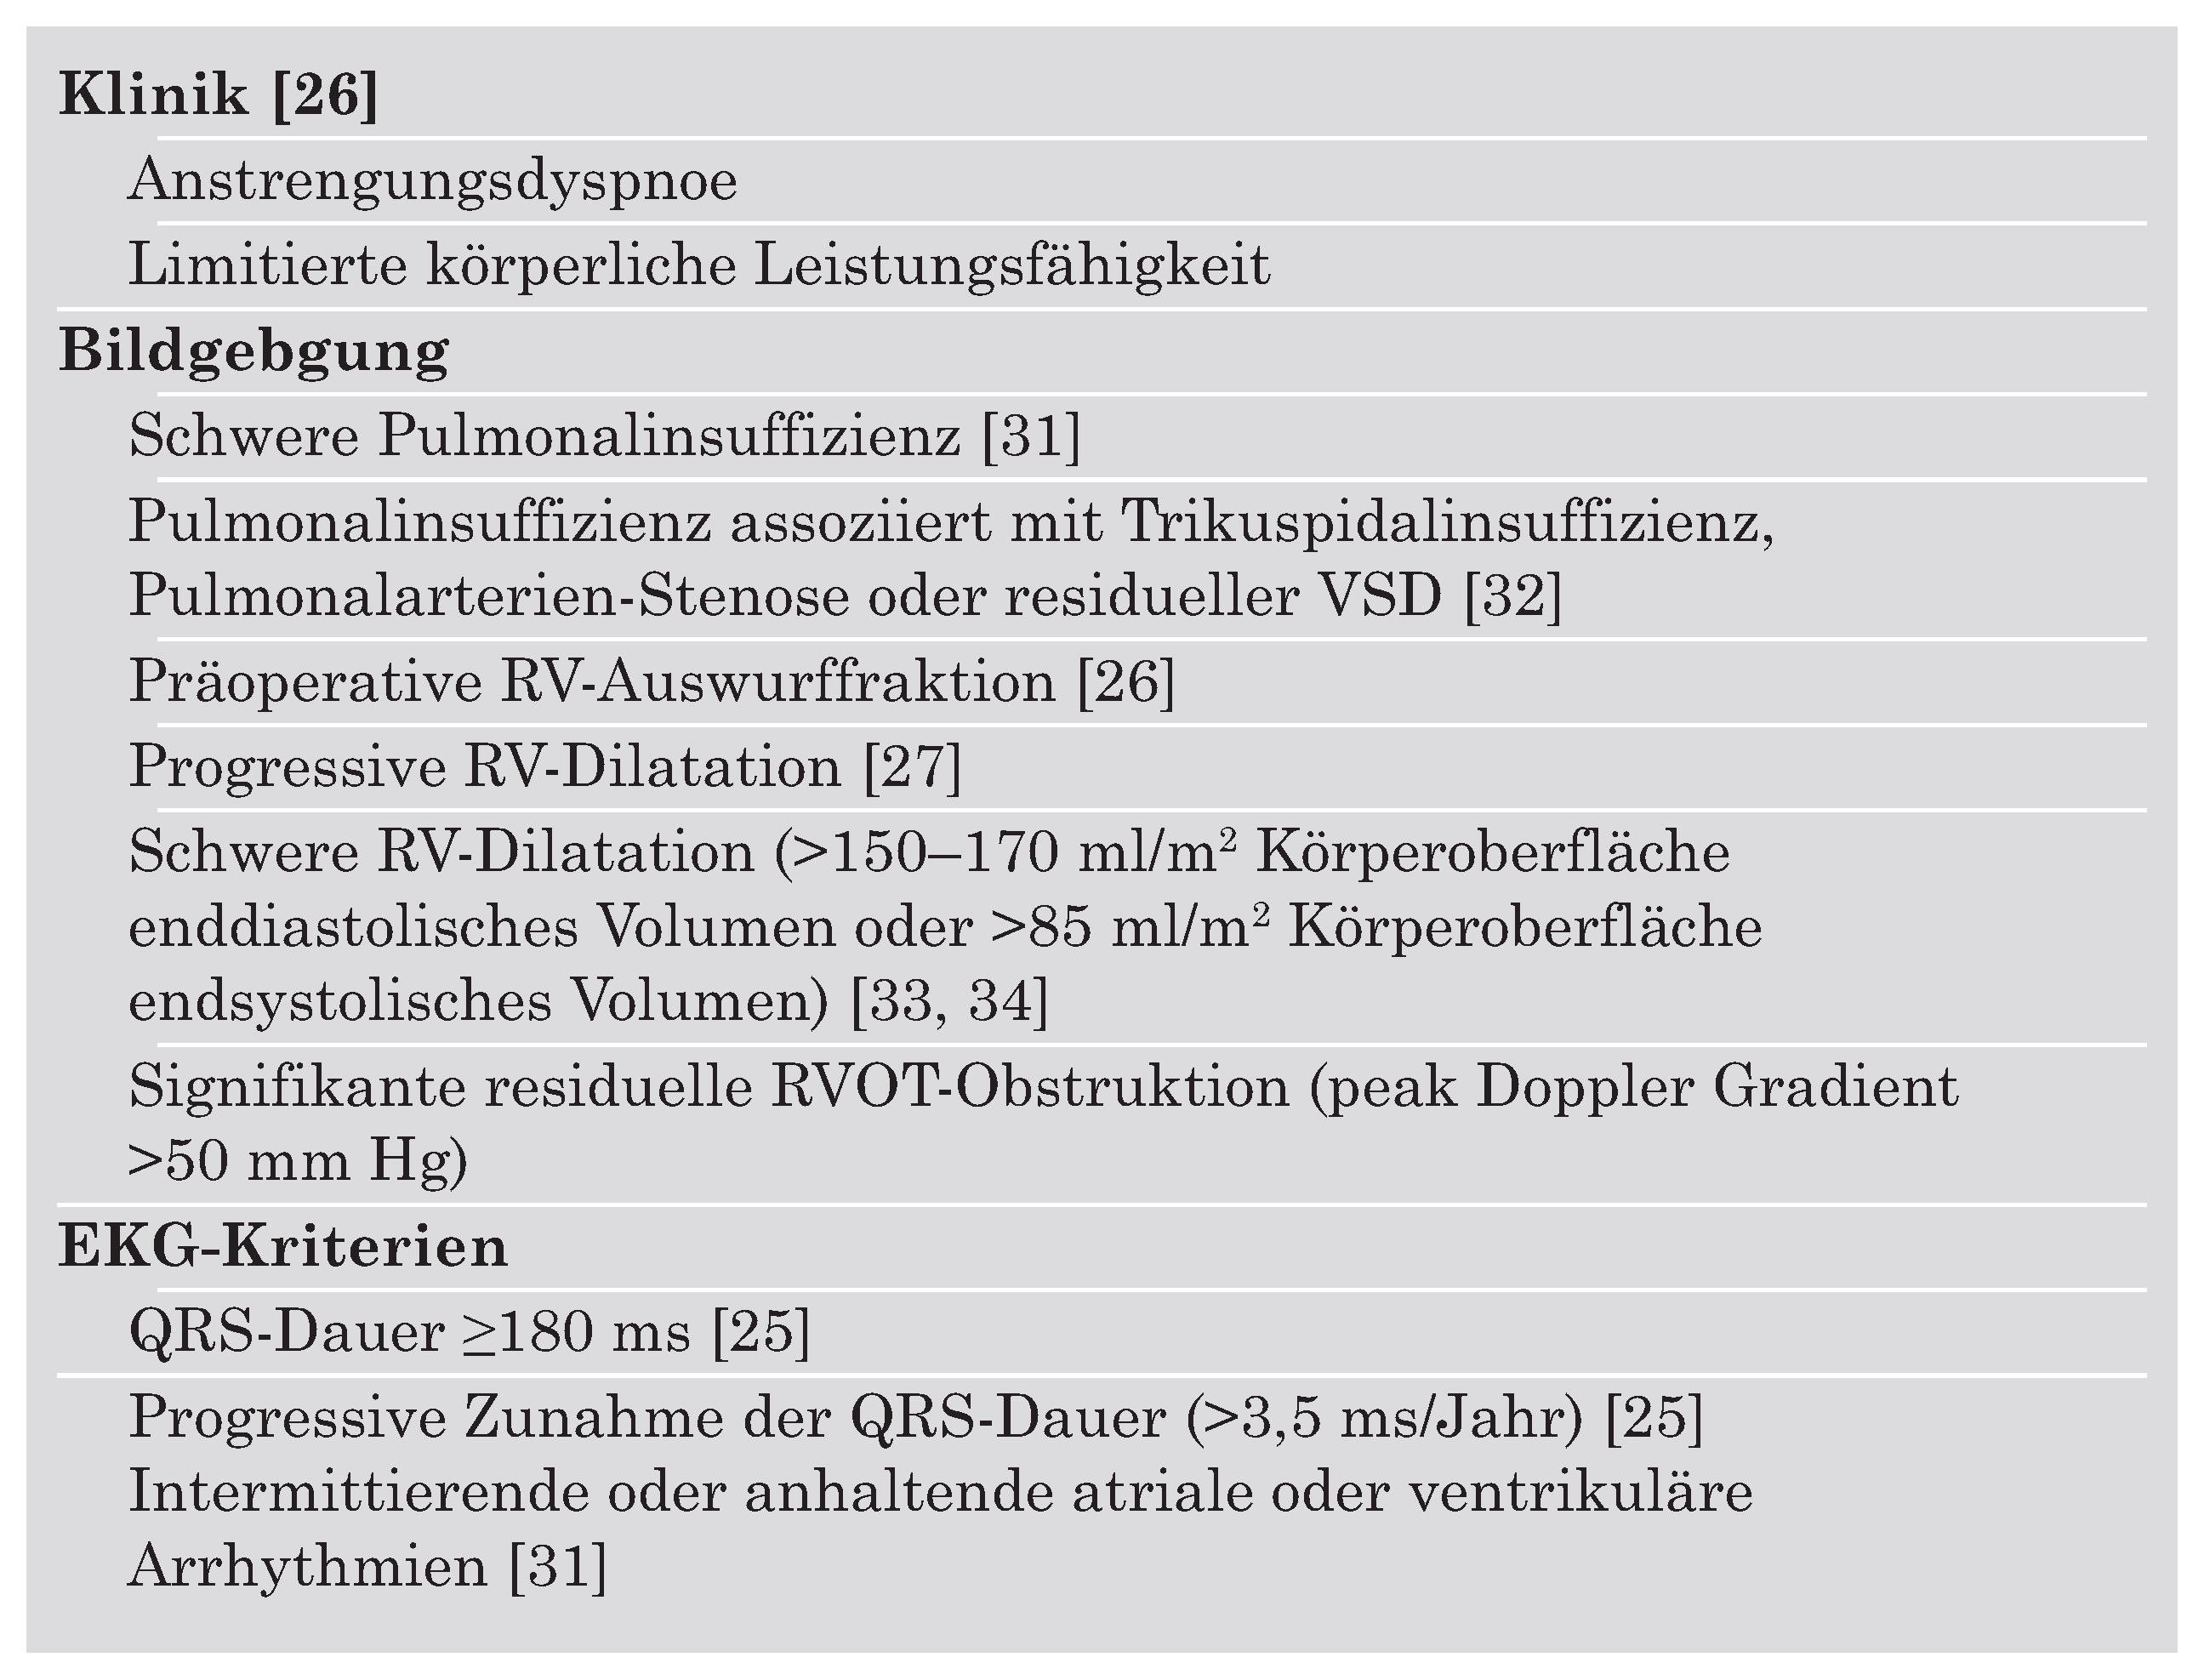

Tabelle 1 macht deutlich, inwieweit der Begriff «Fallot-Totalkorrektur» irreführend ist.

Auch wenn die Langzeitfolgen der schweren Pulmonalinsuffizienz mittlerweile bekannt sind, ist weiterhin unklar, zu welchem Zeitpunkt eine schwere Pulmonalinsuffizienz beim adulten Fallot-Patienten behoben werden sollte. Wird der Pulmonalklappenersatz anhand klinischer Kriterien (Abnahme der Leistungsfähigkeit, Rechtsherzinsuffizienz, Arrhythmien) geplant, besteht die Gefahr dass zum Interventionszeitpunkt bereits eine irreversible RV-Kardiopathie besteht und keine Regression der RV-Volumina oder Verbesserung der RV-Funktion erreicht werden kann [

Tabelle 2 listet nicht abschliessend eine Reihe publizierter Parameter zur Indikationsstellung auf. Zusammengefasst besteht keine allgemein akzeptierte Klarheit über den optimalen Zeitpunkt des Klappenersatzes beim «korrigierten» Fallot-Patienten mit schwerer Pulmonalinsuffizienz, weswegen die Entscheidung individuell unter Berücksichtigung der Klinik und verschiedener Untersuchungsbefunde gefällt wird. Die seit kurzem bestehenden Möglichkeiten des perkutanen Klappenersatzes dürften in Zukunft einen weiteren Faktor darstellen, der den Entscheidungsprozess zur Intervention mit beeinflussen dürfte [